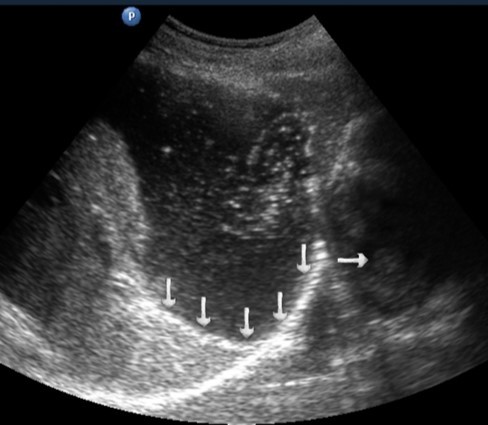

T3 stage of polypoid form was recorded in one case, ulcerative form – in 11 cases, infiltrative ulcerative forms – in 21 cases and diffused infiltrative forms – in 8 cases. The Sonographic features of infiltrative ulcerative form of gastric carcinoma was shown as local uneven thickening of the stomach wall with a length of up to several centimeters with intermittent images and ulceration of the mucosa (Figure 11). The Ulcerative form of gastric carcinoma was shown as a raised margins surrounded by a thickened gastric wall with irregular margins (Figure 12). Gastric carcinomas of diffuse infiltrative form is illustrated as a diffuse thickening of the muscle layer, a smooth contour, discontinuous mucosal image without ulceration and involvement of the serous membrane in the process (Figure 13).

Figure 11.Gastric carcinomas of ulcerating infiltrating forms in the anterior wall of the stomach body of stage T3.

Figure 12.Gastric carcinomas of ulcerating forms in the anterior wall of the stomach body of stage T3. Tumor is manifested with raised margins surrounded by a thickened gastric wall without clear margins.